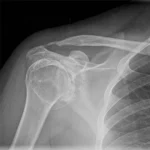

Bone Fractures

Detection of broken bones in any part of the body, including hairline fractures, displaced fractures, and stress fractures common in athletes and active individuals.

Wear comfortable, loose-fitting clothing without metal components such as zippers, buttons, snaps, or underwire. For a chest X-ray, a plain cotton t-shirt without prints or embellishments is ideal. For limb X-rays, wear clothing that allows easy access to the area being scanned, such as shorts for a knee X-ray or a short-sleeved top for a shoulder X-ray. You will be asked to remove all jewelry, watches, piercings, and hair accessories from the scan area. In some cases, you may need to change into a hospital gown to ensure the highest image quality.